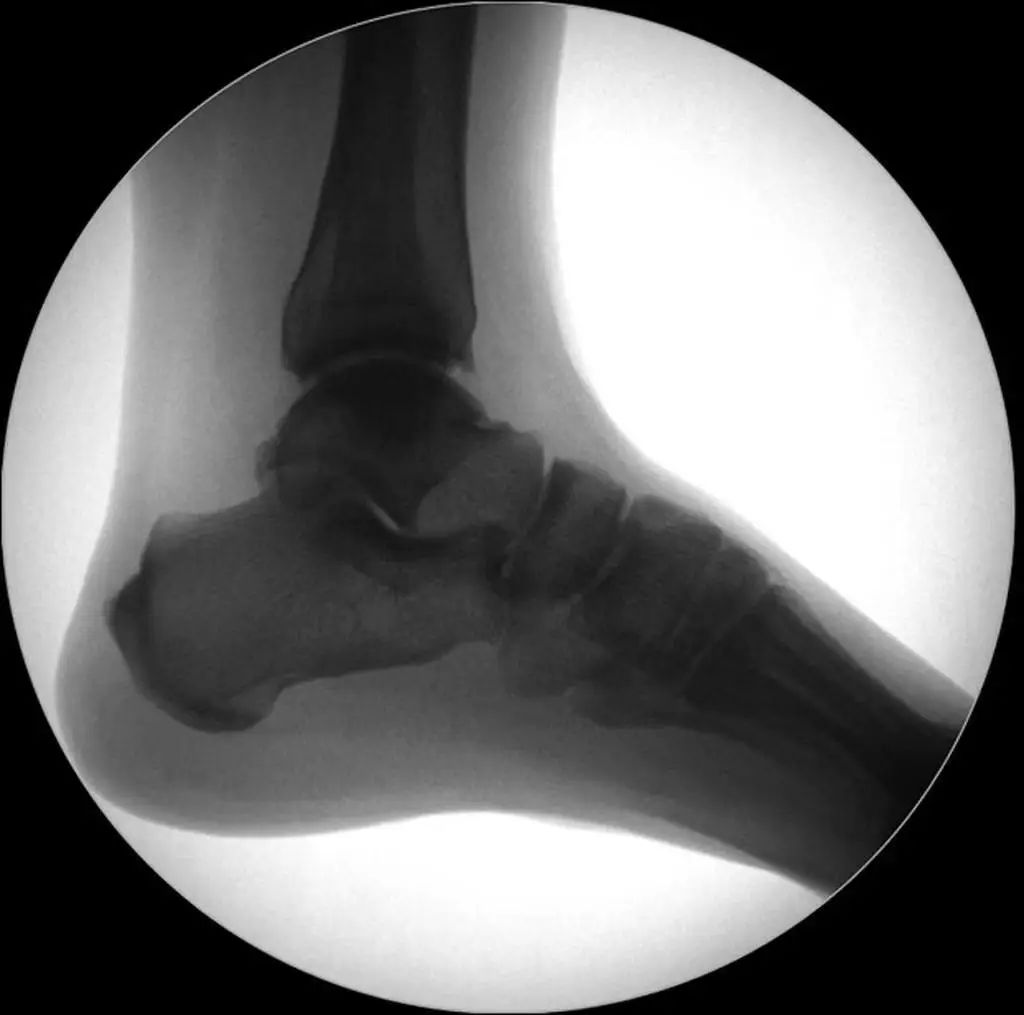

Diagnostic radiographique : L'évaluation standard de l'imagerie de la cheville doit comprendre 3 phases : antéropostérieure (Figure 8), point de cheville (15 ° de rotation interne) (Figure 9) et latérale (Figure 10).

Figure 8 Position avant et arrière

Figure 9 Points de cheville (15° de rotation interne)

Figure 10 Position latérale